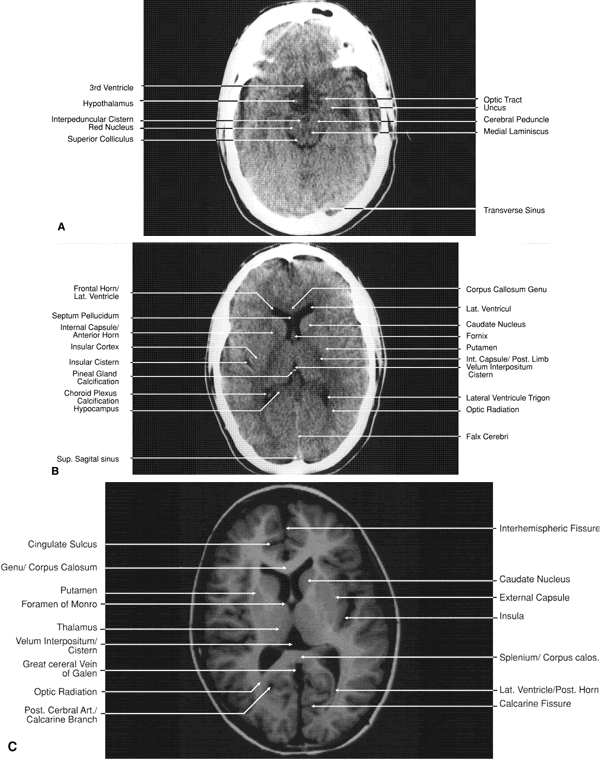

The globe is shown in Figure 12. The orbit and periorbital structures are shown in Figures 13 through 16, and the optic canal is shown in Figures 17 through 26. The cavernous sinus and optic chiasm are shown in Figures 27 and 28, and the posterior visual pathway and cranial nerves are shown in Figures 29 through 33.

Fig. 29. A. Axial computed tomography soft tissue image at the level of the base of skull. B. Axial computed tomography bone window image at the level of the base of skull.

Fig. 30. A. Axial T1-weighted image at the level of floor of orbit and trigeminal nerve. B. Axial T1-weighted image at the level of oculomotor nerve.

Fig. 31. Axial T1-weighted image through the cerebral peduncle at the level of oculomotor nerve.

Fig. 32. A. Axial computed tomography soft tissue image at the level of suprasellar cistern. B. Axial computed tomography soft tissue image at the level of thalamus. C. Axial T1-weighted image at the level of thalamus.

Fig. 33. Sagittal T1-weighted image of the brain through the interhemispheric fissure.